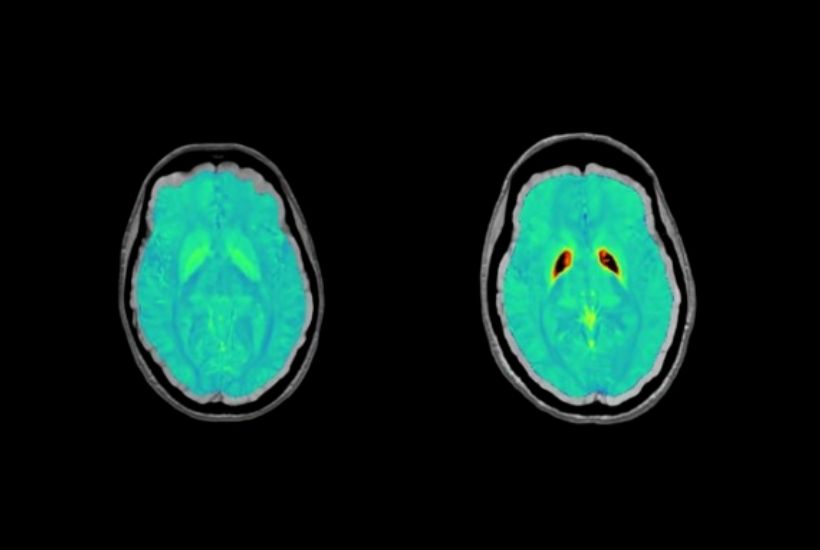

CHU Bordeaux

RARE DISEASE: NBIA

Objectives and results

Identify the regions affected within the deep grey matter:

- kinetics of iron accumulation, the disease’s progression over time

- genetic factors

- link to neurocognitive development from early childhood

- Open the way for the development of therapies